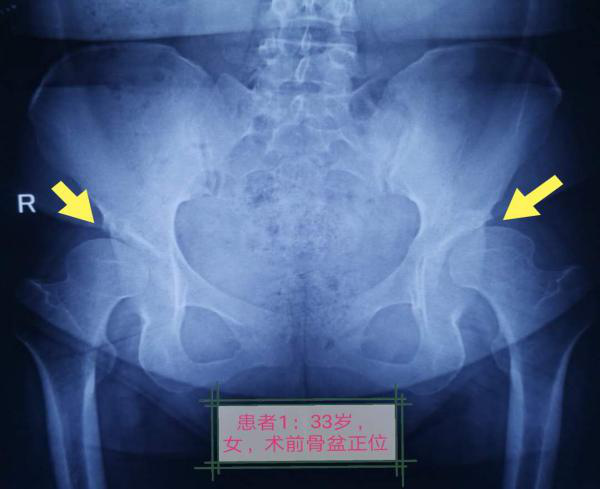

患者一,年龄33岁,女性,双髋疼痛1年左髋加重3月。近期步行超过200米后因髋关节疼痛而不能继续行走,严重影响日常生活工作。患者二,年龄41岁,女性,双髋疼痛3年右髋加重1年,步行超过100米后疼痛不适导致行走功能障碍。入院后完善相关检查,医务人员针对患者伤情的特殊性反复研究、详细计划,在获得家属及患者同意下,实施髋臼周围截骨术。